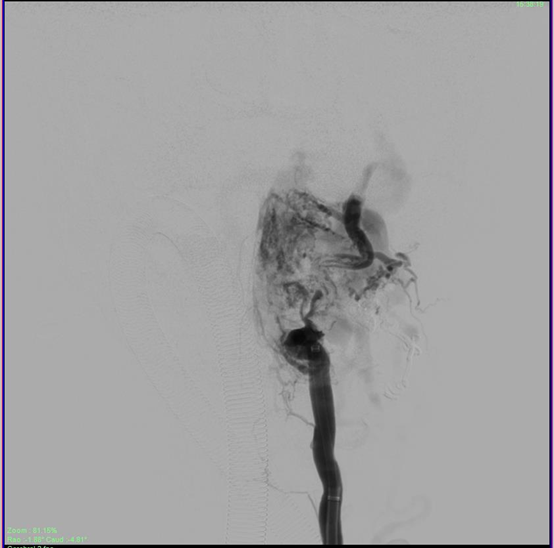

A Contrast Computerized Tomography (CT) scan showed a large vascular malformation around the craniovertebral junction extending from C0 to C3 fed extradurally and extrevertebrally (Figure 2). The patient was explained the nature of the disease as well as the modalities of management. He was then taken up for a Digital Subtraction Angiographic study of the lesion with a concomitant glue/ onyx injection. The angiogram showed a large high cervical epidural AV fistula (EDAVF) being fed by branches from bilateral vertebral, ascending pharyngeal and deep cervical arteries, left more than right (Figure 3). The EDAVF however was exclusively present on the left side. The right sided feeders seemed to be miniscule and to contribute minimally to the flow. The patient was also seen to have a persistent Left Trigeminal artery which augmented flow from the left Internal carotid artery into the Left Vertebral artery. This presented us with an excellent setting for Endovascular treatment for the vertebral feeders.

Figure 2 This shows the CT angiogram with 3D reconstruction of the sequences. The arrow shows the large EDAVF which would have considerably compressed the cord, being fed from the vertebral artery as well as deep cervical branches of the External Carotid system, making this a classic Extradural Arteriovenous Fistula.